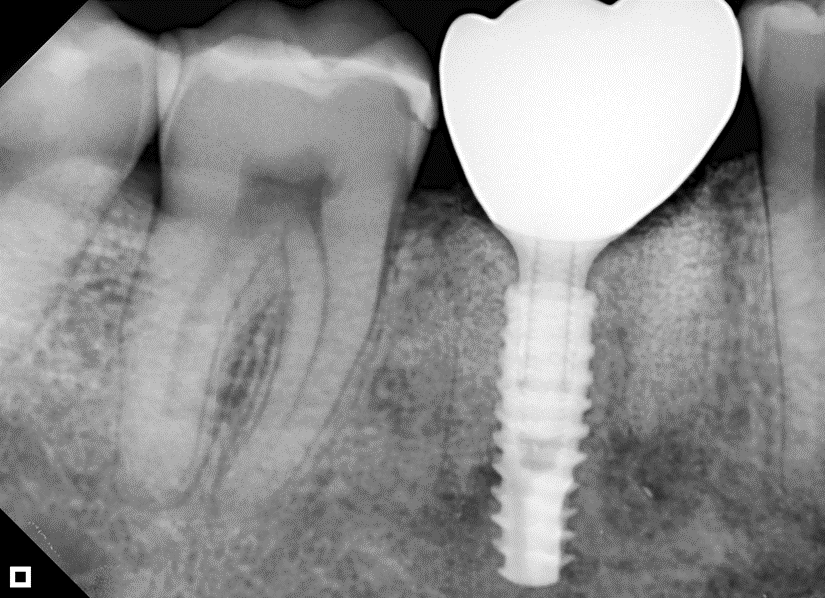

O paciente apresentou fratura vertical mésio-distal no elemento 46. Foi planejada a exodontia minimamente traumática e instalação imediata do implante Maestro Superiore (Implacil Osstem) utilizando uma guia prototipada. Após a exodontia, o implante foi instalado seguindo o protocolo de cirurgia guiada. O GAP vestibular foi preenchido com o Extra Graft. Um cicatrizador personalizado impresso com haletas facilitadoras foi capturado com resina flow e instalado. Após 30 dias, foi realizado escaneamento indireto para obtenção do perfil de emergência, utilizando protocolo digital com sobreposição do cicatrizador escaneado para confecção da coroa definitiva em zircônia policristalina estabilizada por ítria.

A reabilitação imediata de áreas posteriores com implantes instalados no alvéolo pós-extração tem mostrado alta previsibilidade, especialmente quando associada a guias cirúrgicos prototipados e componentes personalizados. O uso de implantes com conexão cônica interna, como o Maestro Superiore (Implacil Osstem), proporciona maior estabilidade mecânica e melhor vedação bacteriana na interface implante/pilar, contribuindo para a manutenção óssea marginal1,2.

A aplicação de biomateriais como o Extra Graft no preenchimento do GAP tem por objetivo preservar o volume alveolar e otimizar a cicatrização3,4. Estudos apontam que o uso de biomateriais associados ao implante imediato resultam em menor reabsorção óssea horizontal e vertical5.